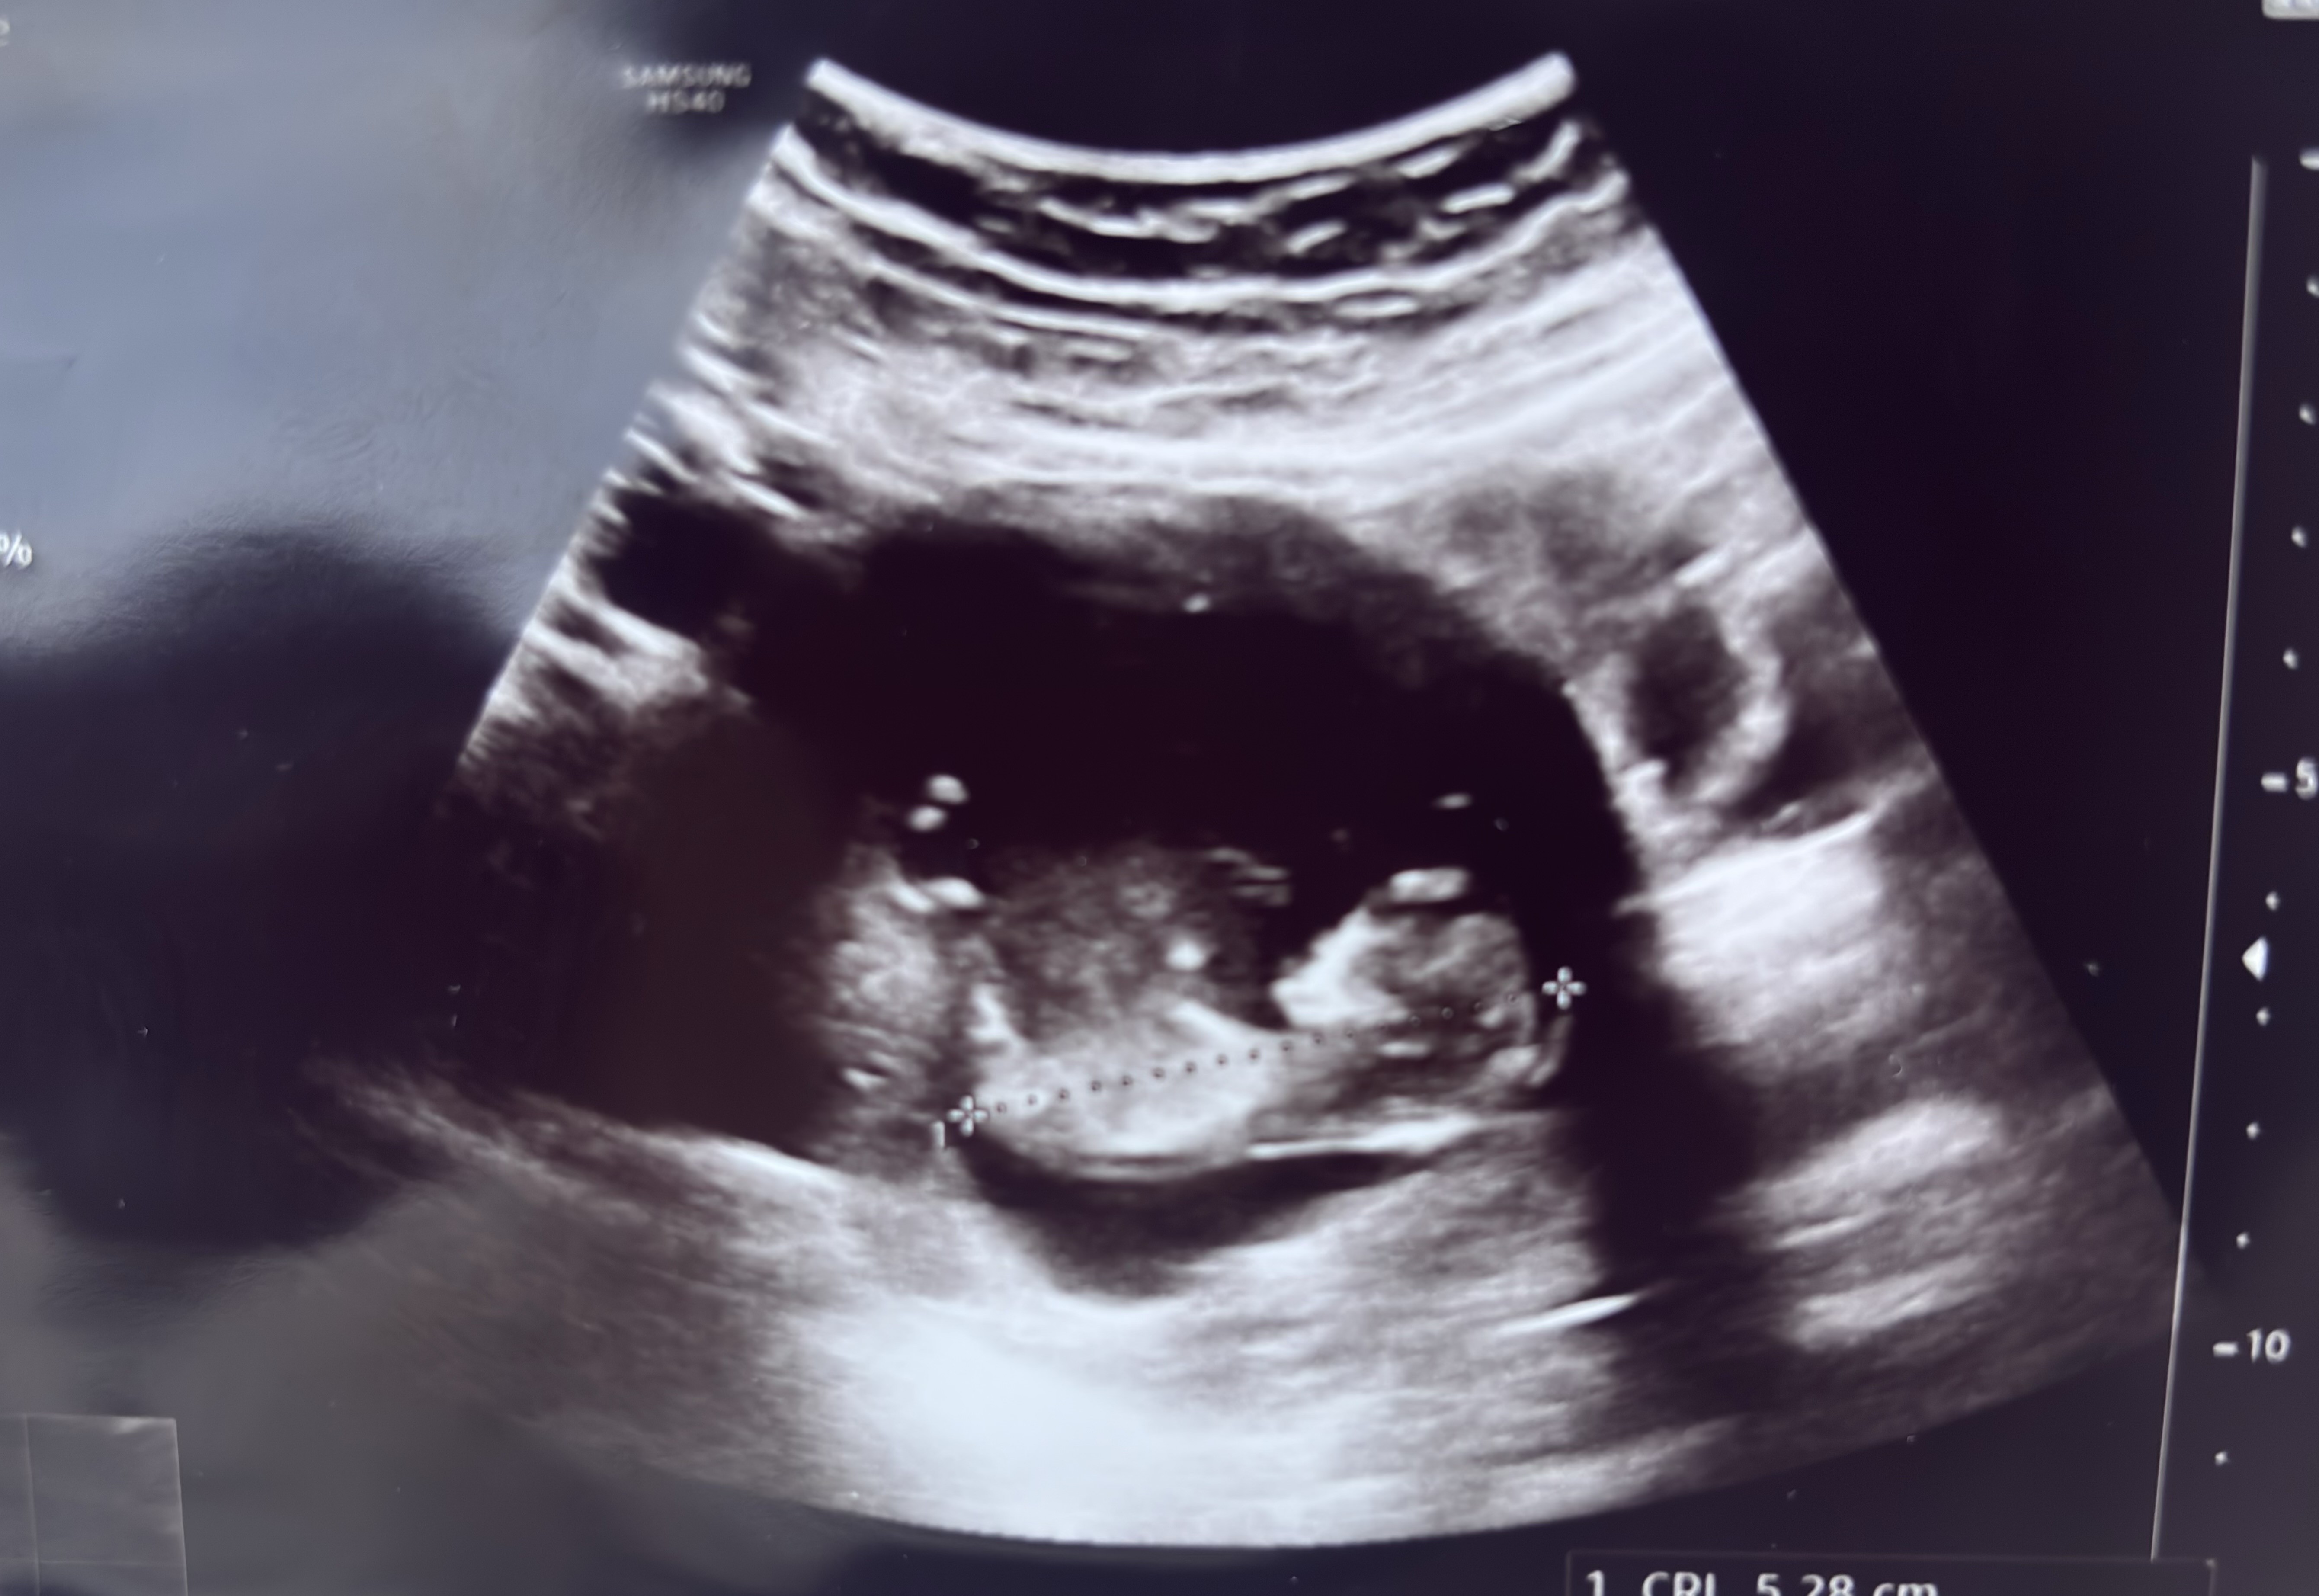

Cudowne wieści, gratulacje @SzklanaKulka i @anusia87, piękne dzidziusieTo i ja swojego bejbuna pokaże! A co![]()